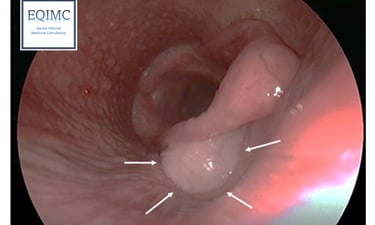

Heeft uw paard last van een aanhoudende of terugkerende hoest? Dan is het aangewezen om een endoscopie (cameraonderzoek) van de luchtwegen te laten uitvoeren. Hoesten wordt namelijk niet altijd veroorzaakt door astma. Tijdens het onderzoek kunnen we ook stalen nemen voor microscopisch en bacteriologisch onderzoek. Op basis van deze resultaten stellen we een behandelplan op maat van uw paard op.

In sommige gevallen is aanvullend een echografie van de longen aangewezen. Dit wordt steeds per situatie beoordeeld en met u besproken.